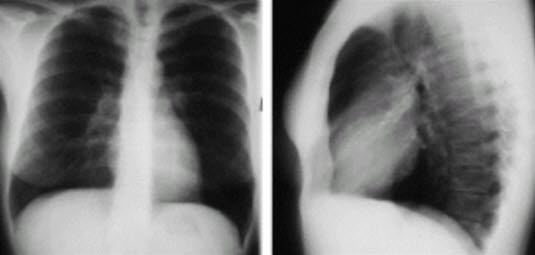

Lungeemboli - røntgen

Rtg thorax, front/side, normal